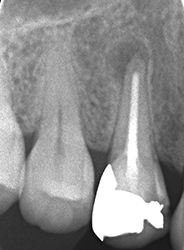

抜くしかない

治療前

治療後

| 主訴 | 10年前に神経を取ってセラミックをかぶせたが一か月前に腫れてきた。歯医者に行って切開して膿を出してもらった。痛みは少し落ち着いたが歯ぐきにおできが出来ていて歯がグラグラする。三日後に抜く予定になっている。 |

|---|---|

| 施術内容 | 保存治療と外科的根管治療の併用 |

| 治療期間 | 3ヵ月 |

| リスク・副作用 | 外科的侵襲 |

| 費用 | 保存治療:138,000円 外科手術:138,000円 相談料:44,000円 |